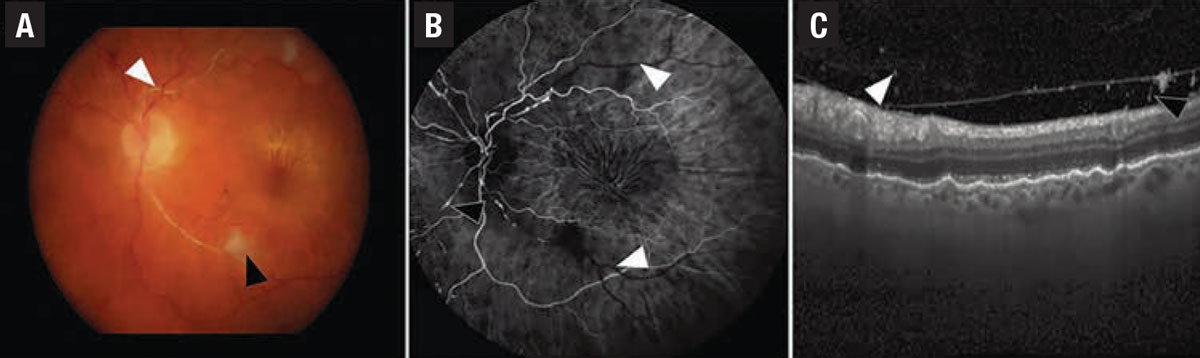

| Figure 1. In a case of iridocyclitis and retinal arterial thrombosis from HAWK and HARRIER, A) color fundus photography demonstrates whitening of the retinal artery consistent with retinal artery occlusion (white arrowhead) and a cotton wool spot (black arrowhead). B) Fluorescein angiogram in the venous phase demonstrates nonperfusion of the retinal arteries (white arrowheads) and arterial box-carring (black arrowhead). C) Spectral-domain optical coherence tomography demonstrates cells in the vitreous on the posterior hyaloid. (Source: Singer M, et al. Ophthalmol Retina. Published online May 8, 2021: doi: 10/1016/j.oret.2021.05.003.) |